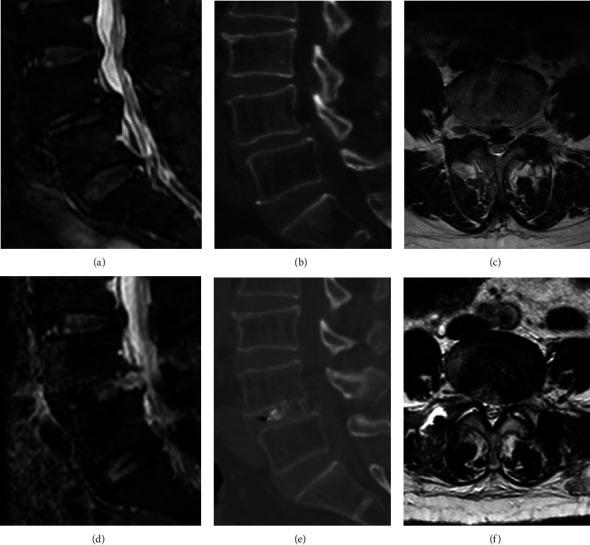

The purpose of this study was to investigate the feasibility and clinical efficacy of the percutaneous bilateral endoscopy technique (microendoscopic trans-Kambin's triangle lumbar interbody fusion + percutaneous endoscopic transforaminal decompression of the lumbar spinal canal, ME-TKT-LIF+ PETD) in the treatment of lumbar degenerative diseases.

From May 2016 to September 2018, 29 patients (16 males and 13 females) who suffered from neurologic symptoms due to degenerative lumbar spine disease and underwent percutaneous bilateral endoscopy technique were enrolled. A microendoscope was used for fusion, and a percutaneous endoscope was used for spinal canal decompression. These patients' perioperative and clinical outcome-related parameters were collected and analyzed.

The mean intraoperative blood loss was 72.8 ± 40.6 ml, the operation time was 87.1 ± 10.1 min, the postoperative ambulatory time was 1.69 ± 1.0 days, the hospital stay was 2.6 ± 1.3 days, and the follow-up period was 22.34 ± 4.2 months. The visual analog scale (VAS) and the Oswestry disability index (ODI) were significantly improved at the early postoperative and last follow-up, respectively. According to the modified MacNab criteria, 11 (11/29) cases were rated as excellent, 15 (15/29) as good, and 3 (3/29) as fair, and the excellent and good rate was 89.7%. Twenty-eight (28/29) cases demonstrated solid fusion, and the fusion rate was 96.6%.